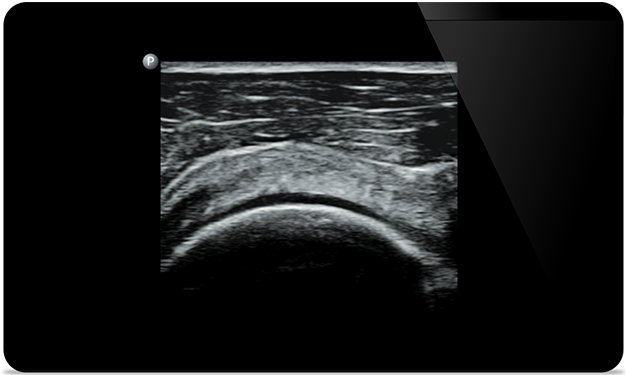

Ultrasound-guided

knee arthrocentesis (Ultraschallgeführte Kniearthrozentese)

Supraspinatus tendon tear (Ruptur der Supraspinatussehne)